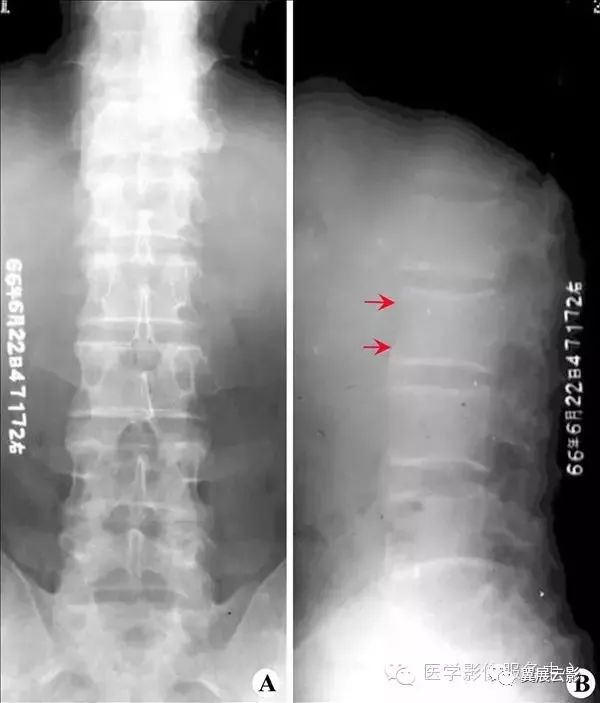

【普通放射图片】:

【影像表现】:X线腰椎正位(A)示腰段脊柱侧弯,腰3/4椎间盘右宽左窄,并见条形低密度改变的“真空征”(↑),腰3椎体左下缘及腰4椎体左上缘呈唇样增生,侧位片(B)见各腰椎前缘唇样增生,腰1/2椎间隙同样见“真空征”(↑)。【影像诊断】:腰椎间盘退行性改变。